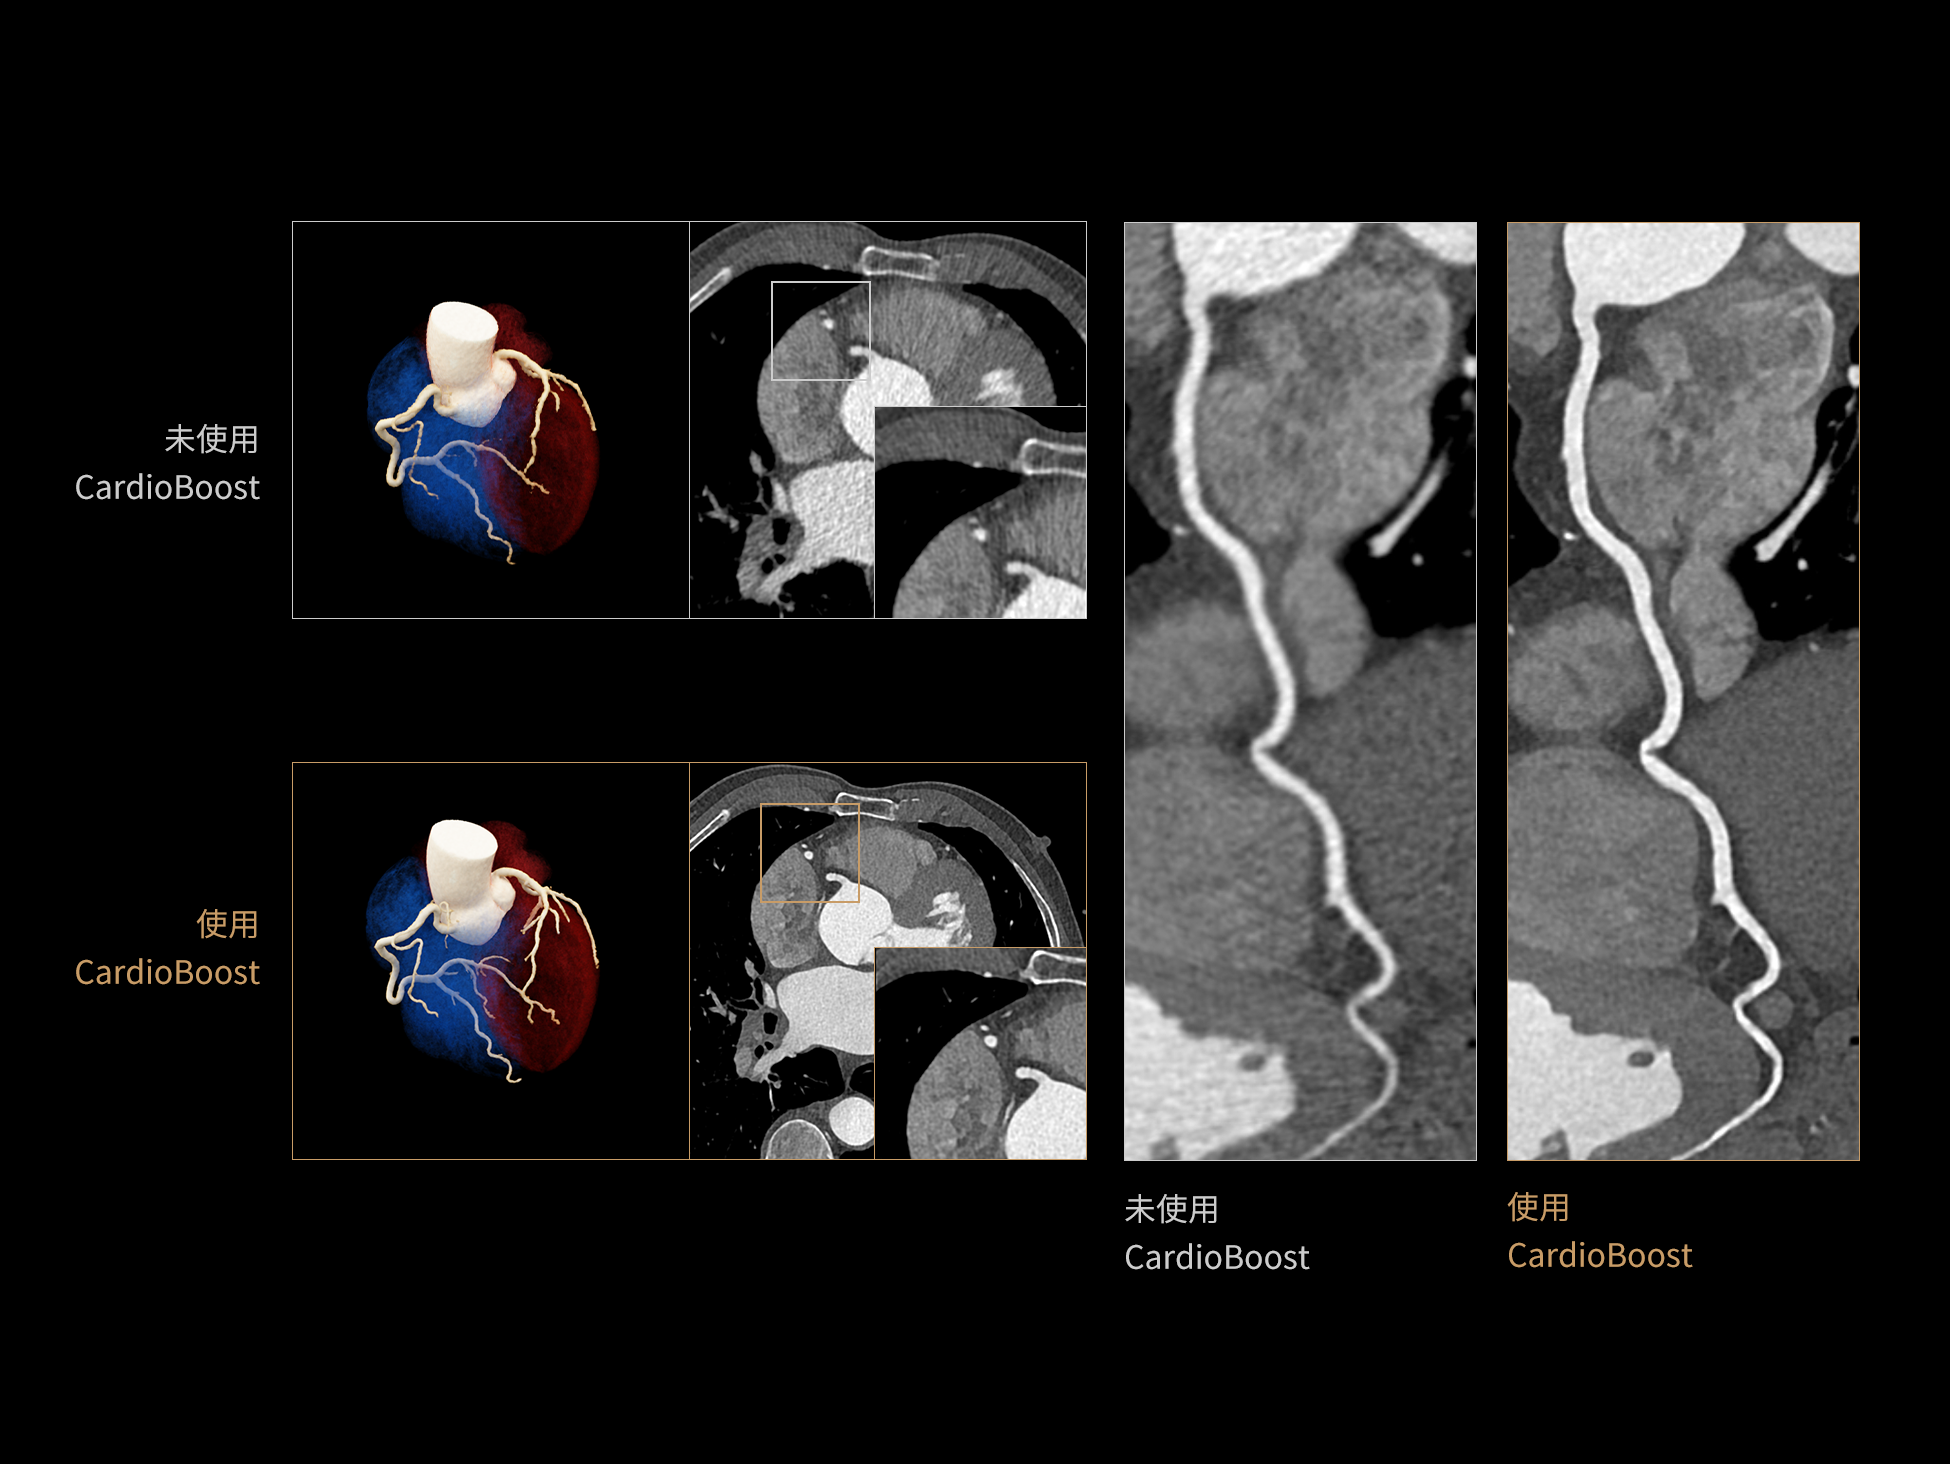

低对比度分辨率提升

相同辐射剂量下